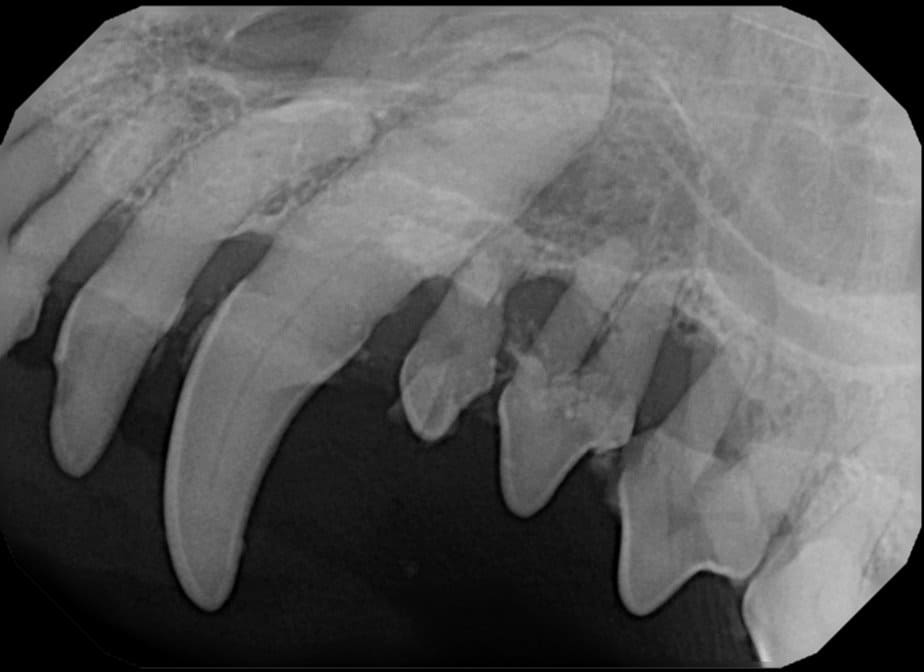

Periodontal disease is extremely common in dogs and cats. Over 80% of dogs and cats over two years of age have some degree of periodontal disease. Periodontal disease is best prevented by yearly professional dental cleanings starting at two years of age and at home brushing at least three times weekly. Brushing should begin at a very early age to allow your new pet to get used to regular brushing. In severe cases of infection or periodontal disease, the teeth may need to be surgically extracted. Extractions should always involve x-rays of the tooth first, as many teeth have multiple roots or may be diseased below where the eye can see. Extracting larger teeth in animals requires oral surgery, equivalent to removing wisdom teeth in people. It is vital that all of the tooth and roots be removed for the periodontal infection to resolve. In cases of important teeth with mild to moderate periodontal disease, multiple periodontal treatments can be offered to help save these teeth.